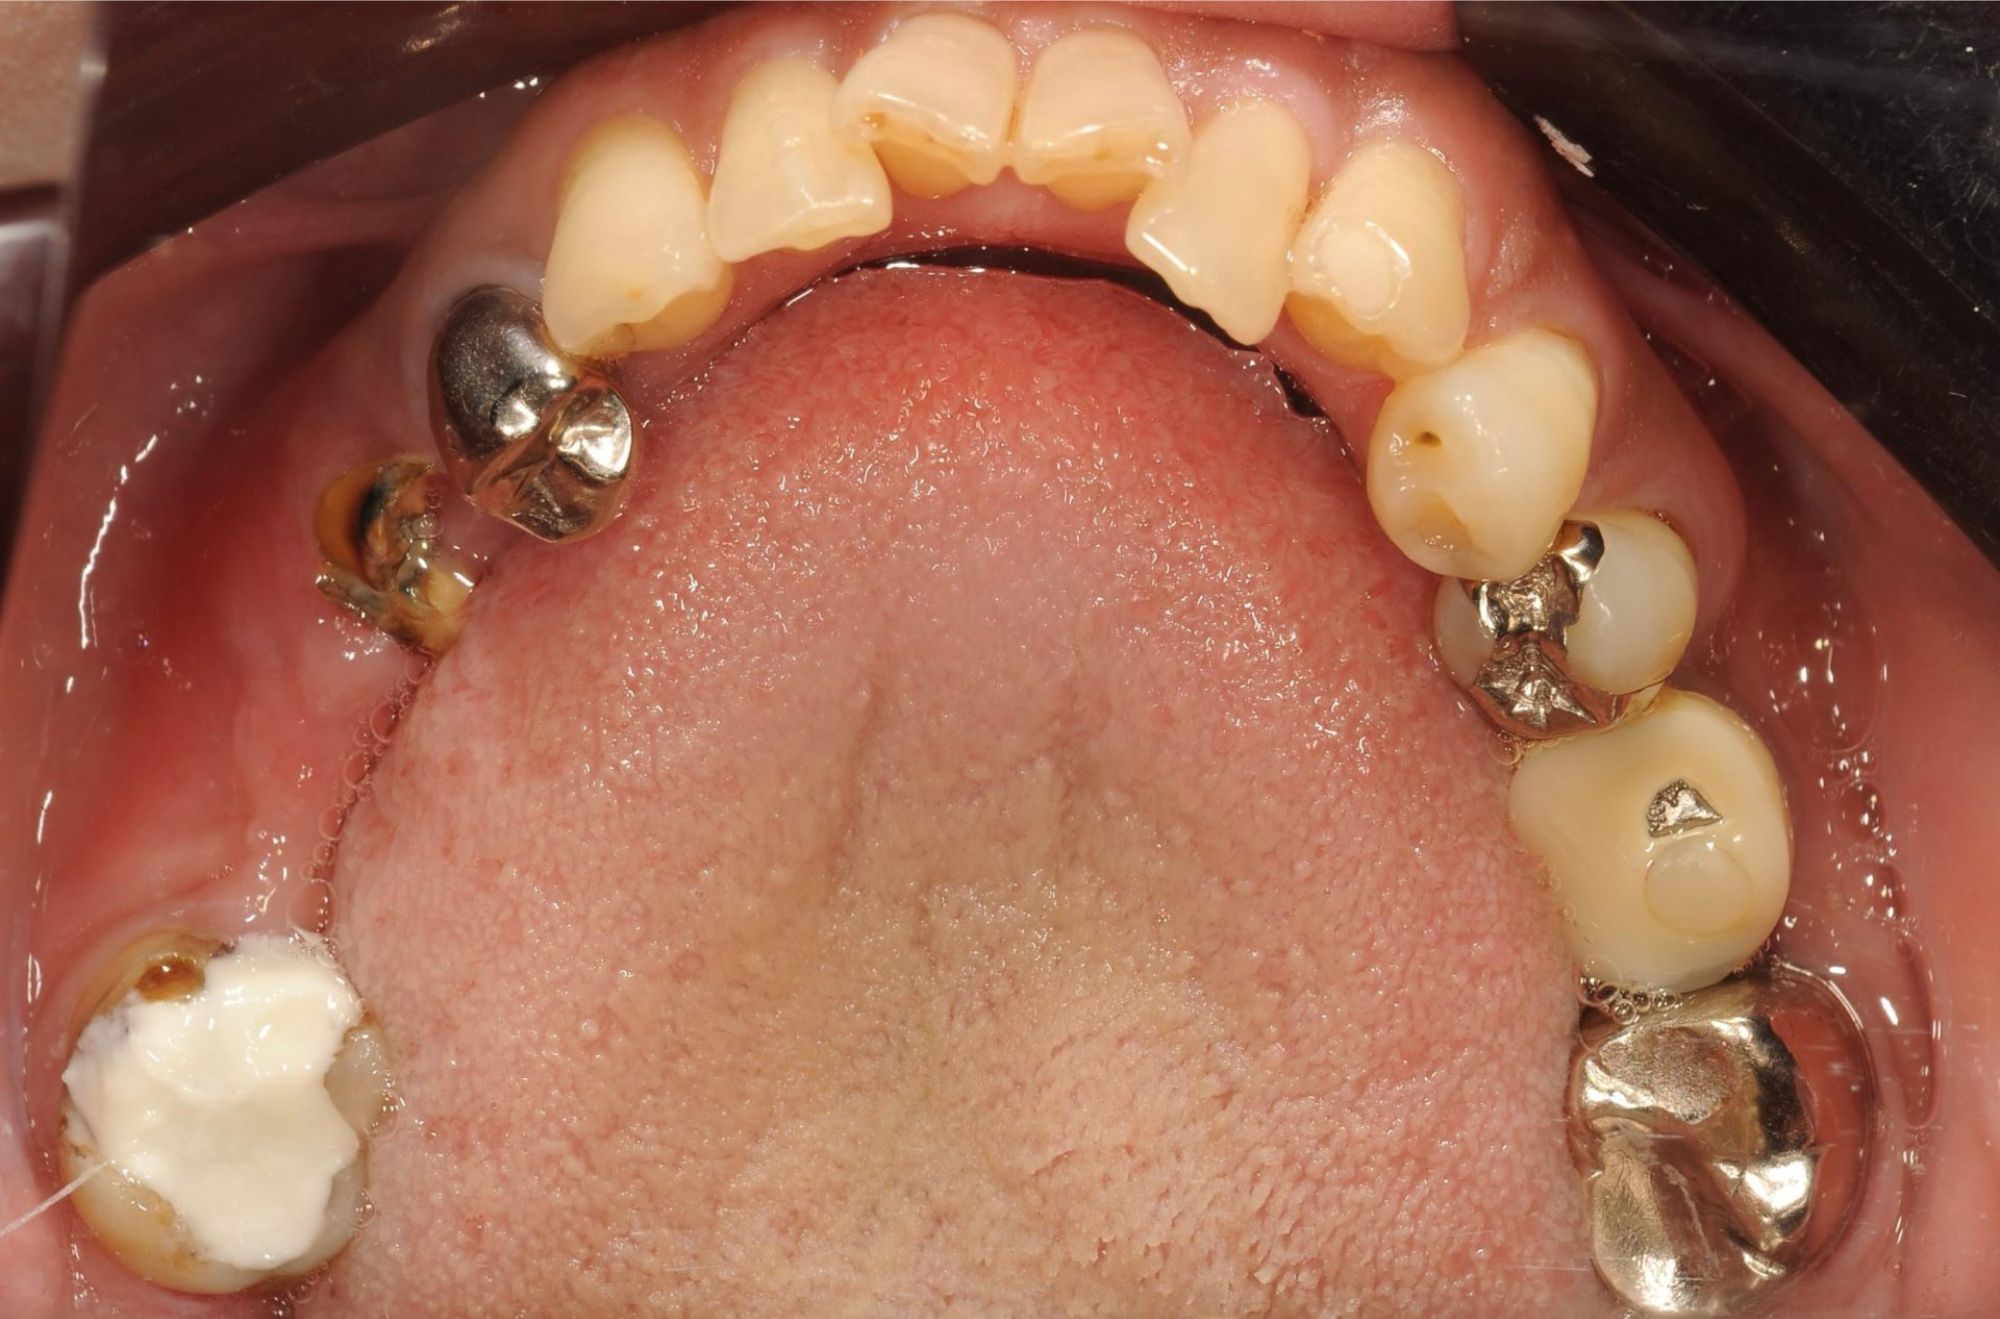

case.01

インプラントで口腔機能の改善

中年の患者様がインプラント治療を希望し来院されました。数本の歯を失っていたため、インプラントを用いて噛む力と審美性を回復しました。治療により、患者様は食事の楽しみを取り戻し、自信を持って笑顔を見せるようになりました。